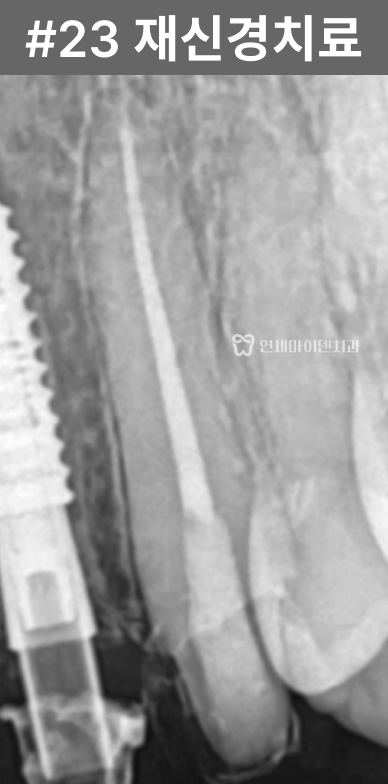

반면, 보존이 가능하다고 판단된 앞니는

신경치료를 진행했고

내부를 철저히 소독한 뒤

경과를 관찰했습니다.치료 결과

임플란트로 치료한 앞니는

안정적으로 자리 잡았고,신경치료를 시행한 치아는

치근단 낭성 병변이

자연스럽게 치유되면서

추가적인 치근단 수술 없이

회복을 확인할 수 있었습니다.